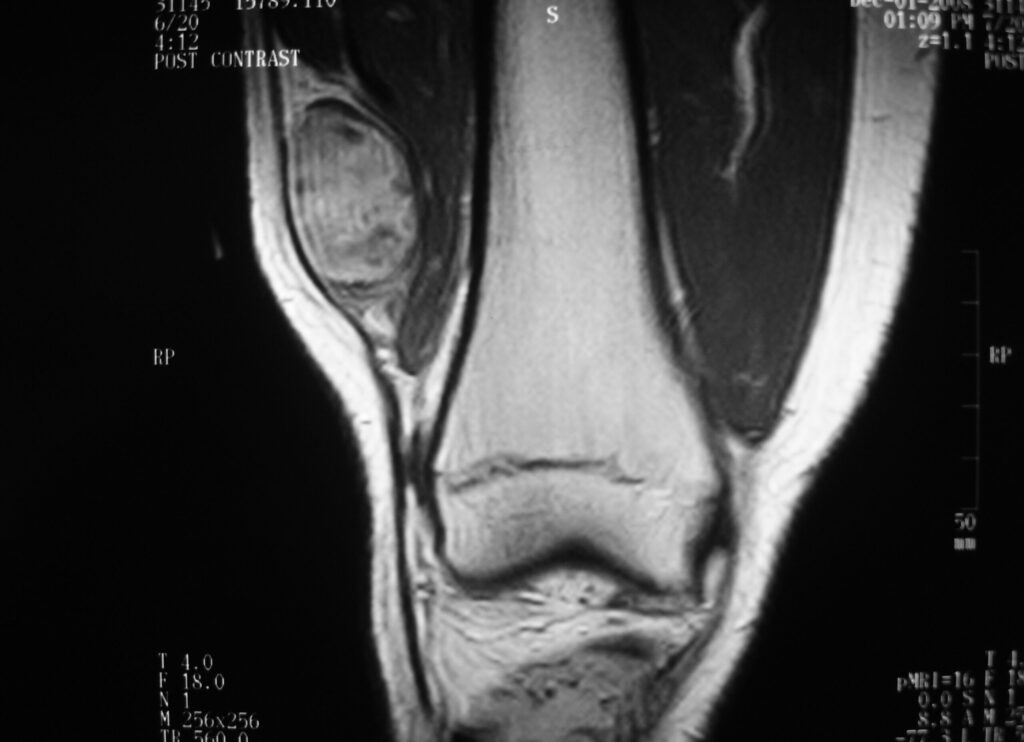

MRI

Shows multiloculated, heterogeneous mass.

“Triple Signal Intensity sign”; hypointense, isointense and hyperintense with fat on T2 – weighted MRI imaging. This sign is present in 30 to 50% of the cases. (Fig.3)

Under contrast enhancement Synovial Sarcoma appears heterogeneous and demonstrate areas of nodular enhancement.

In approximately 30% of cases a multiple vascular cannel may be identified

Synovial sarcomas may have a cystic appearance and are often mistaken for ganglion cysts especially those adjacent to tendons and in the foot and ankle.